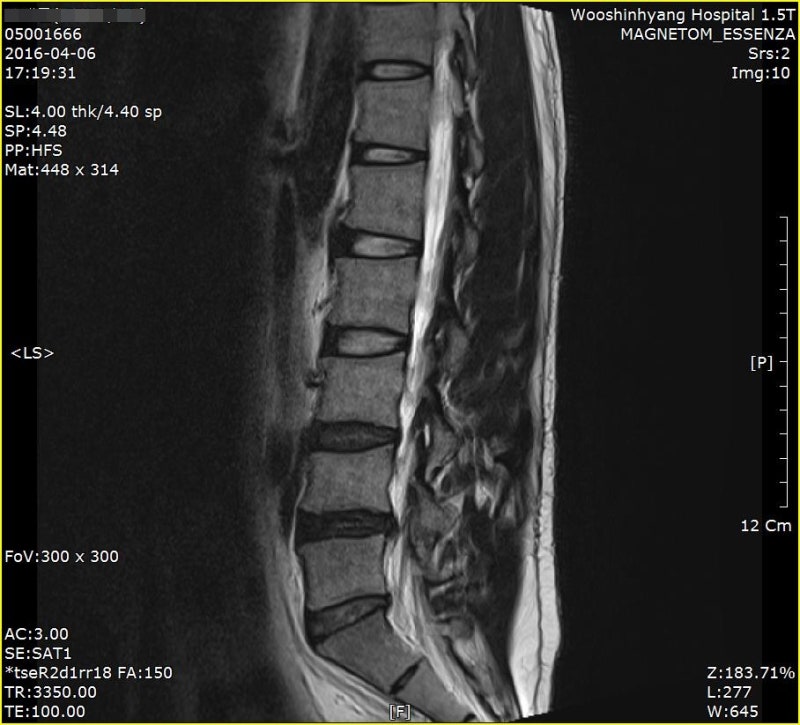

디스크 검사 및 치료 디스크 질환은 MRI와 엑스레이를 중심으로 검사를 실시합니다. 디스크가 발생한 경우에는 당연히 디스크를 치료해야 하지만 이를 검사할 때 척추의 구조나 상태를 종합적으로 진료해야 합니다. 요추의 인대나 힘줄은 어떤지, 척추의 구조는 어떤지, 또 디스크의 파열 정도나 상태를 파악해서 치료를 진행하는 것이 중요합니다. 디스크 치료는 보존 치료를 통해서도 호전을 기대할 수 있을 정도로 예후가 좋은 편이지만, 만약 특별한 상황이라면 수술적 치료를 고려할 수도 있습니다. 디스크 질환은 사람마다 다를 수 있으므로 정확한 검사와 진단으로 치료를 진행하는 것이 좋습니다.